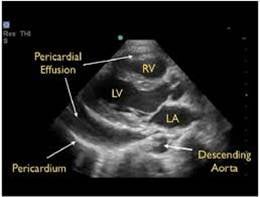

Effusion, Trauma, and Tamponade

- Pericardial effusions are common and range from benign to life threatening.

- In contrast to an effusion, epicardial fat pads are isolate to the anterior of the heart and often have increased echogenicity.

- In the setting of trauma, significant effusion may signify cardiac injury.

- The parasternal long axis view can be helpful in distinguishing between pericardial (anterior to descending thoracic aorta) and pleural (posterior to the DTA) effusions.

- Findings of tamponade on echocardiography include right ventricular diastolic collapse, right atrial systolic collapse, plethoric IVC, and increased inflow variation.19

- Pericardial tamponade is potentially lethal without intervention. Intuitively POCUS can decrease time to intervention although to date this is supported only by weak evidence.20

- Epicardial fat pads are usually isolated to the anterior heart and have internal echoes. Pericardial fluid usually collects in the dependent posterior pericardial space and can be seen surrounding the myocardium anterior to the descending aorta. A left sided pleural effusion will be located posterior to the descending aorta.

- Figure 15. Parasternal long axis showing pericardial effusion anterior to descending thoracic aorta

- Clotted blood in the pericardial space may have more hypoechoic appearance.

- Cardiac tamponade is a clinical diagnosis. Place the echocardiographic findings in the context of the patient’s clinical status.